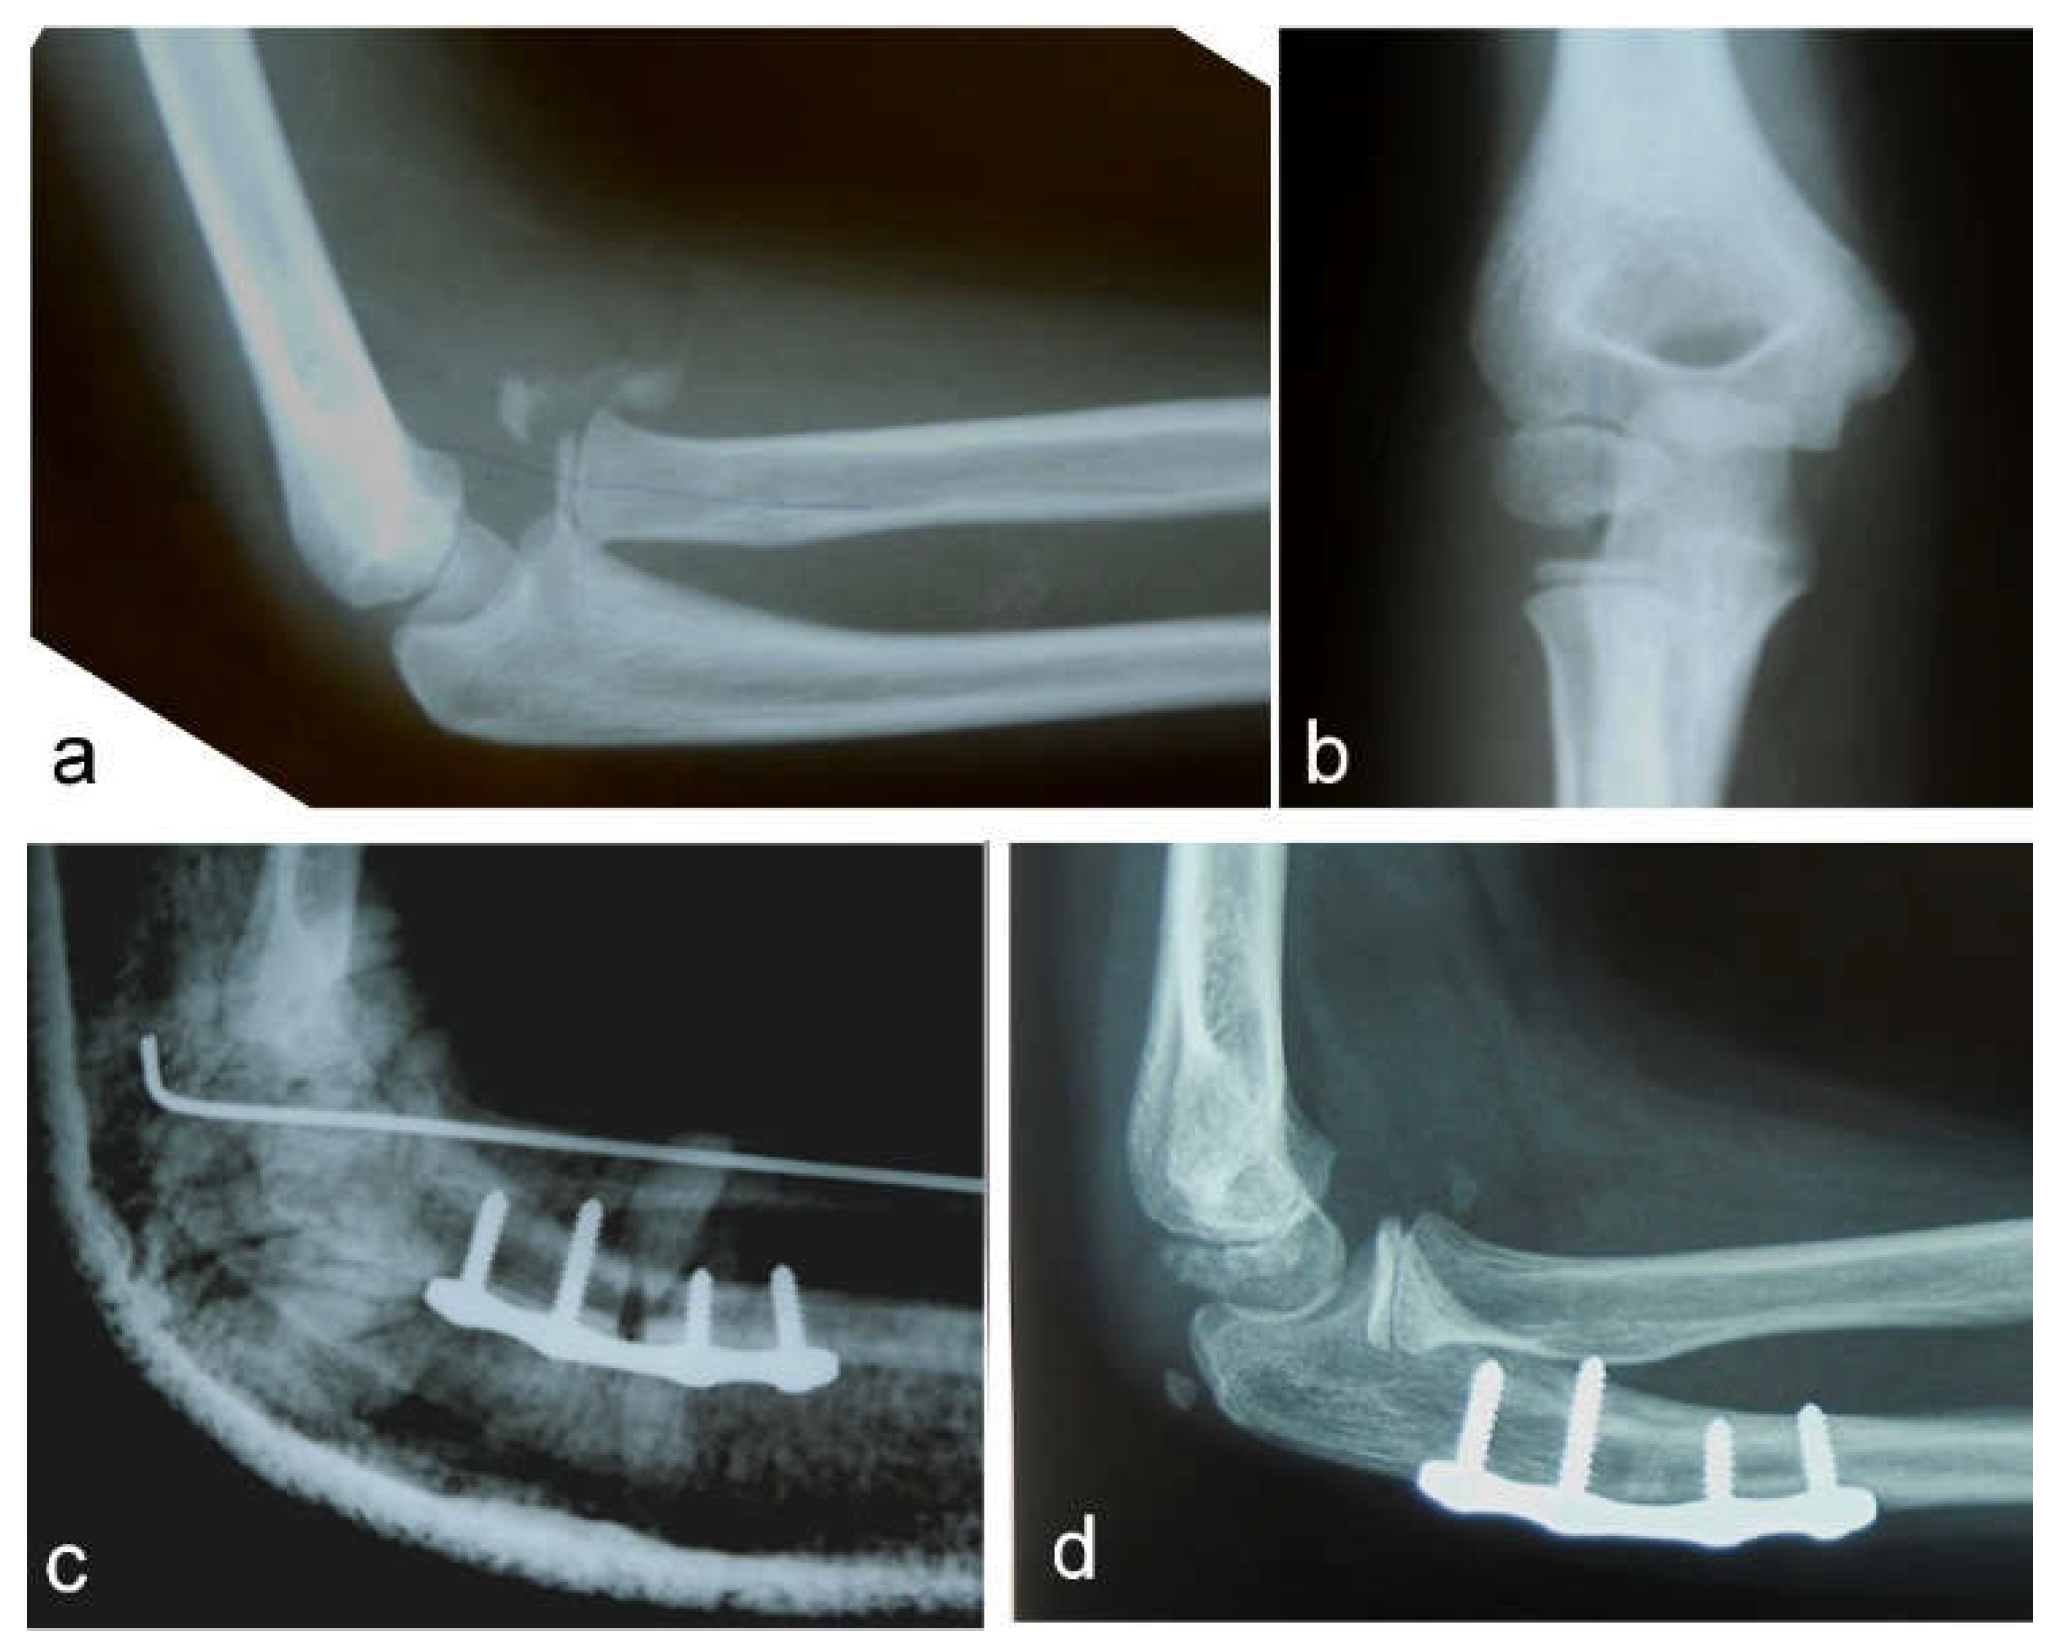

Nine patients had a Bado type I injury, with the radial head displaced anteriorly, and four patients had a Bado type III injury, with lateral and anterior radial head displacement. All patients were treated as soon as possible after a diagnosis of the missed Monteggia fracture was established. The period from diagnosis to surgery varied from 2 days to 2 weeks. An autologous bone graft, harvested from the iliac crest, was used in only one case to fill the gap after osteotomy of the ulna. Another nine osteotomies of the ulna and three osteotomies of the radius healed without bone grafting. All osteotomies of the ulna and two osteotomies of the radius were stabilized with plates and 4–8 screws (Figure 1 and Figure 2).

Figure 1.

Neglected Monteggia fracture: (a) anterior dislocation of the radial head with heterotopic ossification visible on a lateral view; (b) AP view; (c) high posterior angulation and elongation osteotomy of the ulna stabilized with a plate and four screws. Transcapitellar fixation of the radial head with Kirschner wire; (d) the reduced radial head and healed ulnar osteotomy are visible on a lateral X-ray before removal of the plate and screws.

All the patients in our study were operated on shortly after being diagnosed with a chronic Monteggia lesion. However, there is no need to hurry. Thorough preoperative planning of the reconstructive procedure is very important. A set of correct radiographs in true AP and lateral projection of both injured and uninjured forearms should be obtained [9]. If any discrepancy in the physiological curve of the ulna exists, it should be corrected by ulnar osteotomy. Straightening the natural ulnar curve may result in an incomplete reduction of the radial head, re-dislocation or even late dislocation [24]. We observed re-dislocation of a reduced radial head in one patient as the cause of their chronic Monteggia lesion. His ulna fracture was originally stabilized with a retrograde elastic titanium nail, but progressive loss of reduction with angulation of the ulna occurred. That was left unnoticed until the follow-up for cast removal, which was 4 weeks after the surgery. Revision and fixation with a plate and screws were subsequently performed. We believe that retrograde ESIN may provide insufficient stabilization of the ulnar fracture in a Monteggia injury. Anterograde ESIN through the olecranon entry point may be a better solution. Alternatively, open reduction and plating of the ulna may be performed. If malalignment of the ulna exists, then an osteotomy of the ulna should be the first step in the treatment of chronic Monteggia fractures, especially 3–4 months from the initial injury. A posterior angulation and elongation osteotomy of the ulna, as described by Bouyala [25], is currently the preferred method. Performing an osteotomy high in the metaphyseal region of the proximal third of the ulna may decrease the risk of delayed union or nonunion. Eight of our patients were treated this way (Figure 1). Other authors prefer a more distal osteotomy at the site of maximal angulation of the ulna [26]. Sliding [2] and “Z”-lengthening [27] osteotomies of the ulna have been recently published. In two of our patients, correction of ulnar angulation was performed at the level of a fracture of the ulna. Both patients underwent surgery 5 weeks after their injury, and their fractures, although consolidated, were not completely healed; we decided to correct the deformity at that level (Figure 2). Kim et al. [28] recently performed a 3-dimensional analysis of the deformation of the ulna in patients with chronic radial head dislocation. They found not only angulation but a complex torsional deformity of the ulna. This may explain why a simple angulation-lengthening osteotomy of the ulna may not be completely effective in all cases, especially in Bado type III cases, as reported by Delpont et al. [14] and was observed in one of our cases. Correction of such a complex deformity requires complex correction in two or three planes.